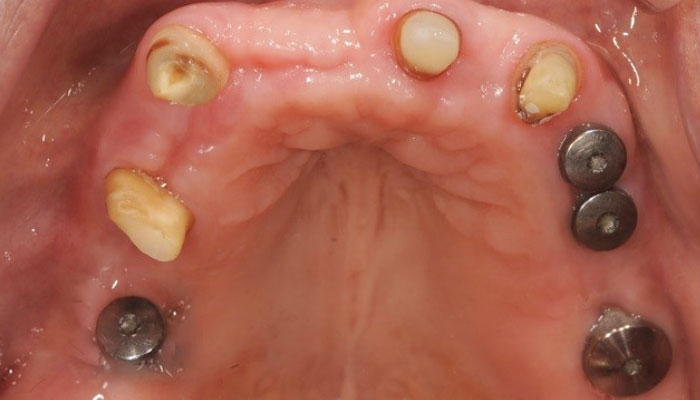

術前術後の口腔内者写真

治療前

治療前症例写真

3-2.歯周病治療

歯の足りないところだけに、6本のインプラントで固定式の歯を入れることになりました。黒い丸のところにインプラントが入っています。

6本のインプラントはすべて、フルジルコニア+スクリュー固定で製作されています。

6か所の穴がスクリューホールですが、歯が入ったら同色のレジンでふさいでしまいます。